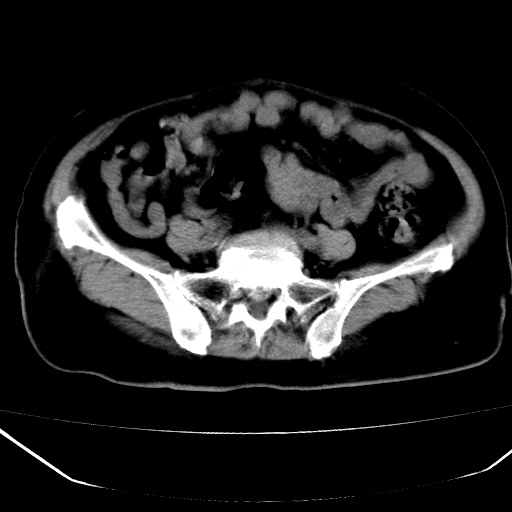

患者,女,74岁,无不适,b超示盆腔包块。

子宫前上方巨大脂性肿物,肿物边缘为较厚软组织密度影,其内缘欠光整,脂性密度中央见结节状软组织密度影“漂浮”,肿物与子宫前壁关系密切,考虑1脂肪瘤2皮样囊肿3肌瘤脂样变

ct值-90hu